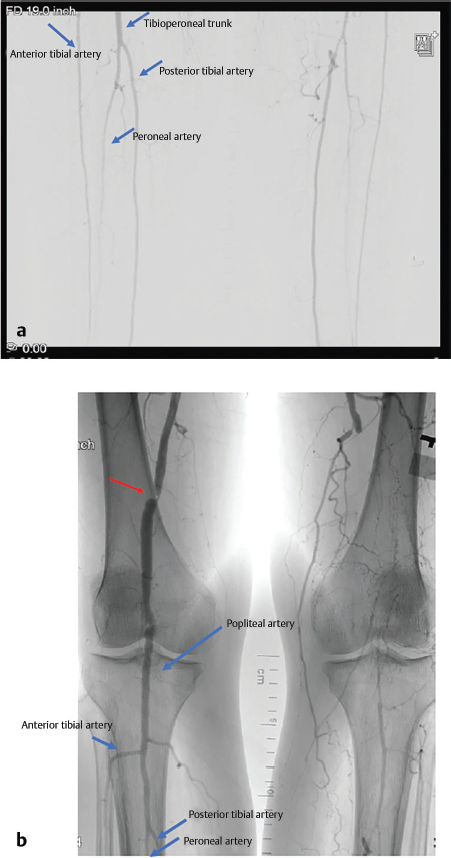

19 Lower Extremity Reconstruction Abstract This chapter will review the principles of lower extremity reconstruction after trauma. It will review preoperative assessment of blood flow and zone of injury, as well as reconstructive options. The readers will be able to analyze a given lower extremity injury and determine an appropriate operative intervention, and integrate the free flap failure algorithm in the management of postoperative complications. Keywords: lower extremity reconstruction, zone of injury Six Key Points • Determine the etiology of the wound. • Always assess the zone of injury. • Determine baseline function and neurovascular status prior to reconstruction. • Vascular integrity is key to lower extremity reconstruction. • Post-operative rehabilitation protocols are key to a successful outcome • Realistic expectations must be set for outcomes. A patient presents with an open leg wound after a motor vehicle crash. There is visible soft tissue loss. 1. What do you do? The injury is at least Gustilo 3b injury, which can be identified by the size of the defect (> 1 cm) and periosteal stripping, which leaves the bone exposed. If there is associated arterial injury, the classification is a 3c injury. This classification is useful because type III injuries require flap coverage of bone (Table 19.1). 2. What do you do? Assuming the patient is otherwise stable and orthopaedic surgery has adequately fixed the bone, preparations should be made for coverage. This begins with a full lower extremity examination, including motor and sensory function, and palpation of pulses. Imaging is then ordered. An angiogram is ordered. 3. The angiogram is shown in Fig. 19.1. Describe what is in the angiogram. The first vessel to come off of the popliteal artery is the anterior tibial artery, which appears the most lateral. The popliteal continues as the tibioperoneal trunk, and the next vessel, which appears medial to the anterior tibial artery, is the peroneal artery. The vessel then continues as the posterior tibial artery. 4. If only the posterior tibial vessel is open, what do you do? In that case, the case is more complex, but an end-to-side anastomosis can be performed. Table 19.1 Gustilo’s and Anderson’s classification of open tibial fractures